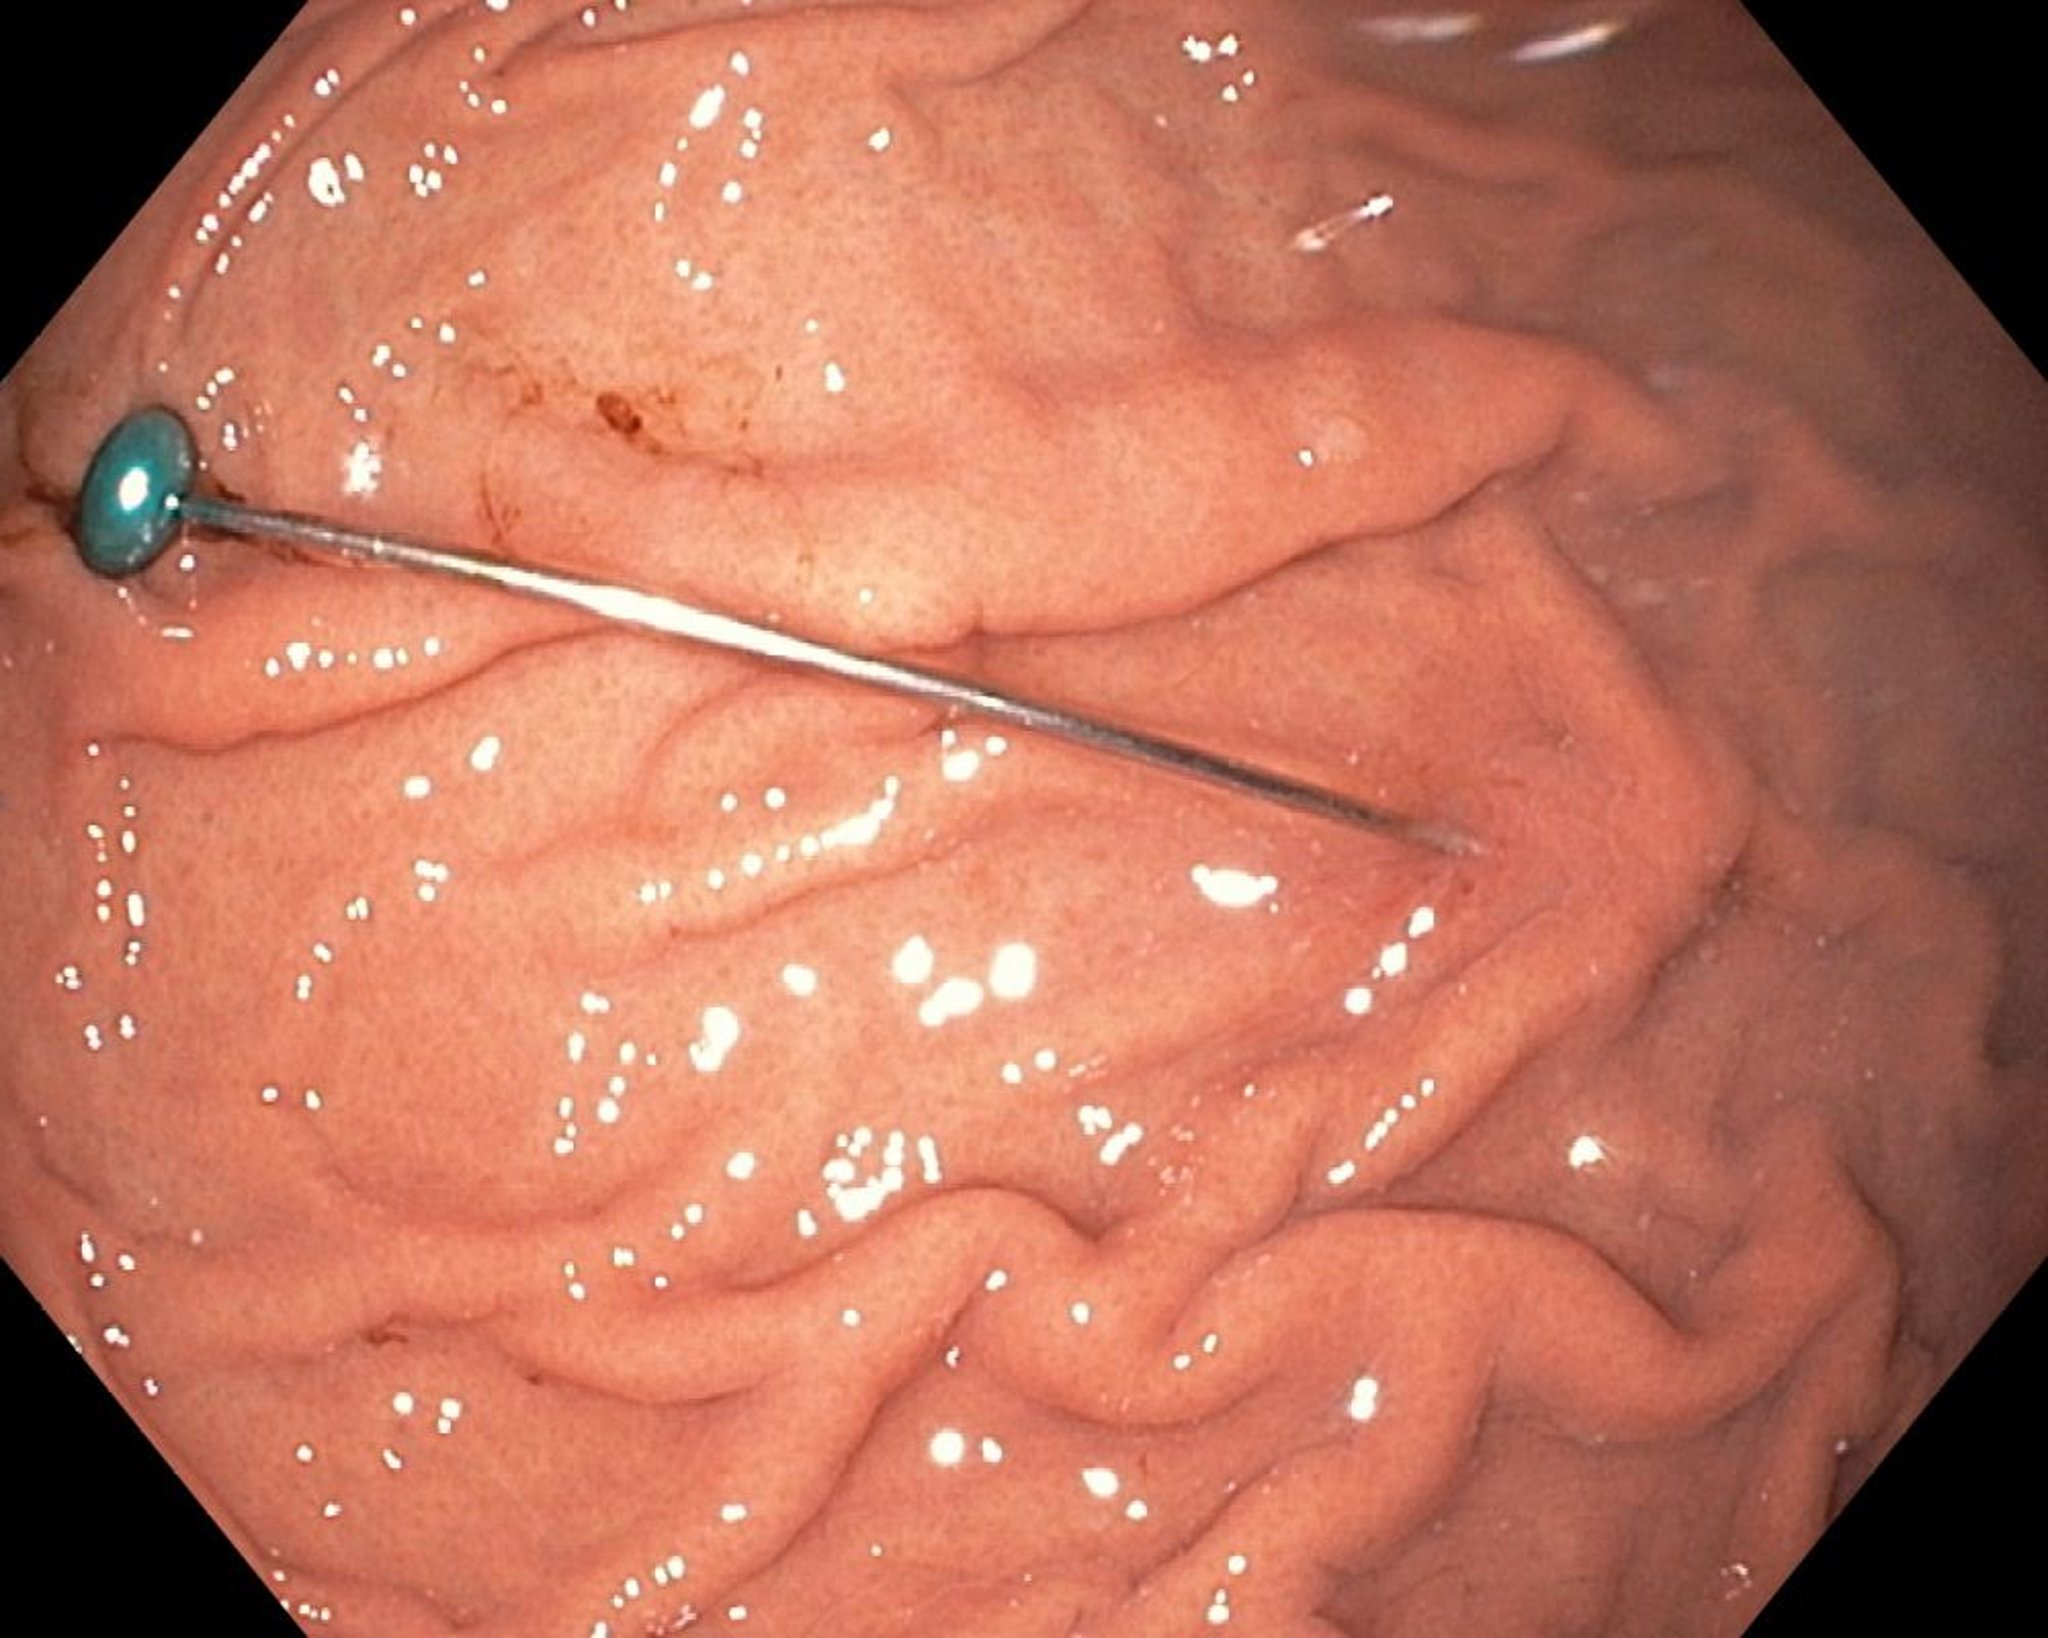

Esta imagen muestra un cuerpo extraño afilado en el estómago.

Imagen proporcionada por Uday Shankar, MD.